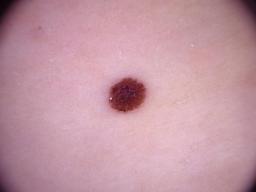

{

"age_approx": 70,

"anatom_site_general": "upper extremity",

"concomitant_biopsy": false,

"diagnosis_1": "Benign",

"diagnosis_2": "Benign melanocytic proliferations",

"diagnosis_3": "Nevus",

"diagnosis_confirm_type": "single image expert consensus",

"image_type": "dermoscopic",

"lesion_id": "IL_7986377",

"melanocytic": true,

"sex": "male"

}